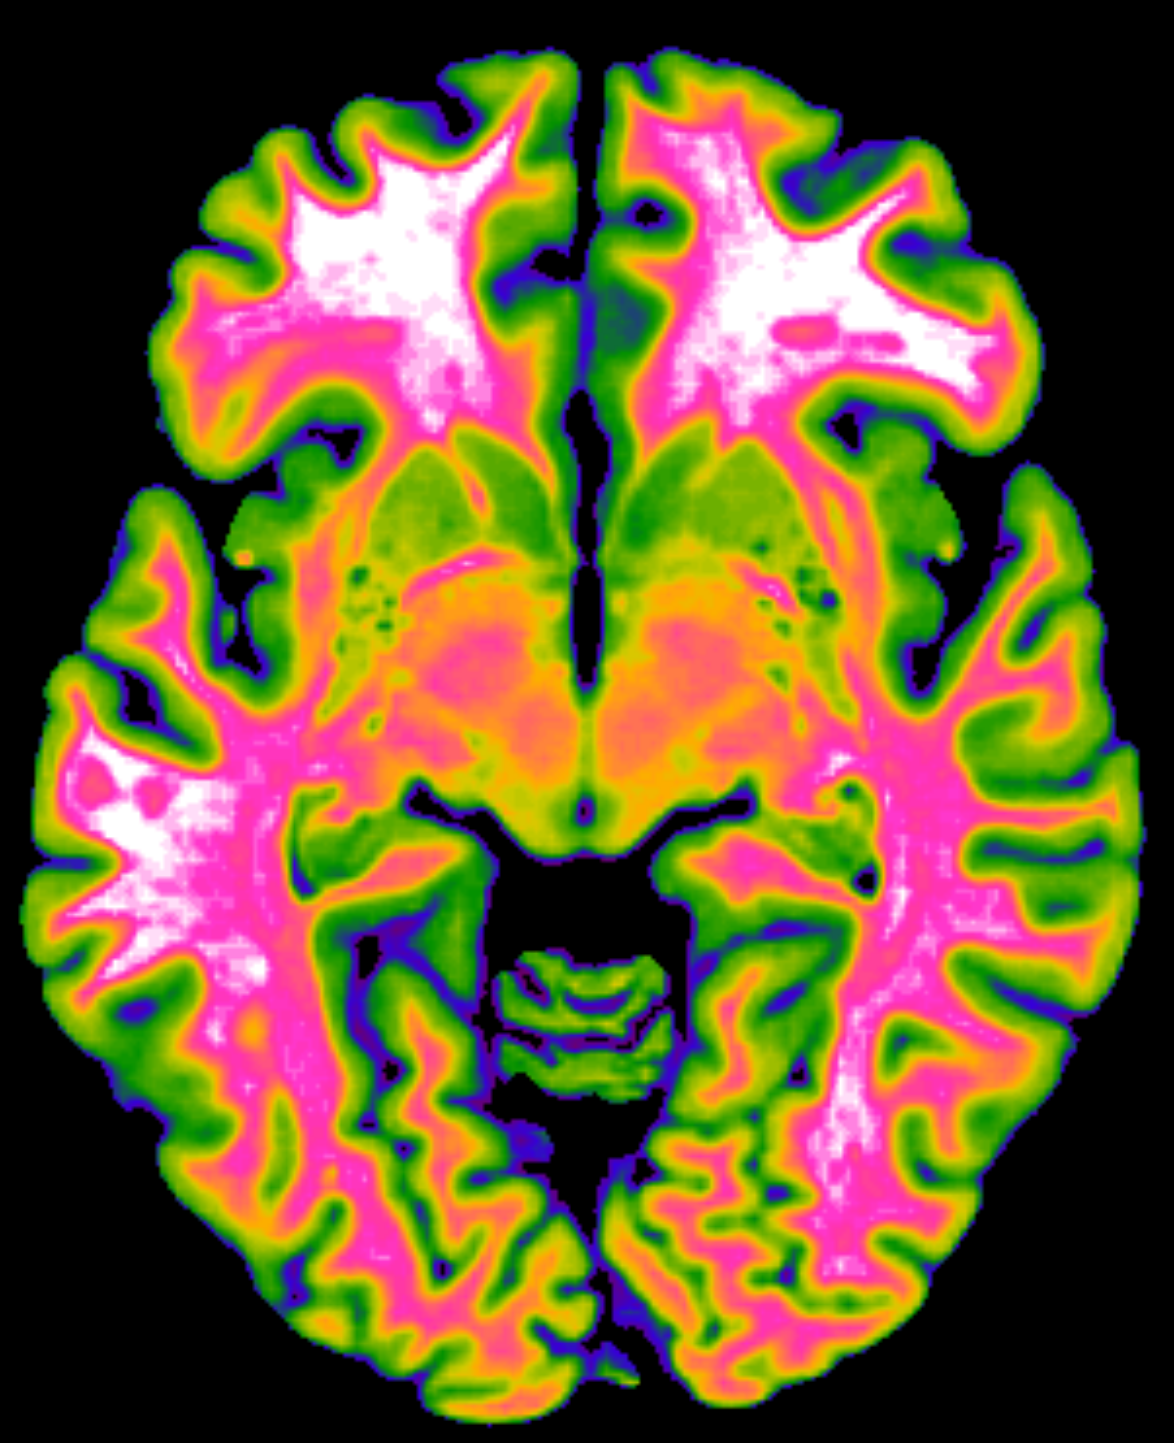

Insights from pharmacological imaging of the human brain

This project aims at understanding the neuronal underpinnings of anhedonia and hedonic experiences by merging two distinct fields, empirical aesthetics and pharmacological/clinical neuroimaging. With the recent rise of ketamine as an effective antidepressant and description of its effects on hedonic tone, a unique opportunity arises to investigate hedonic experiences, their neuronal signature, and their relation to well-being in healthy subjects and patients with anhedonia. This project will not only probe the relevance of the hedonic experience and its neurobiological correlates for ketamine’s antidepressant effects, but will also implement a causative approach in empirical aesthetics enabling a systematic manipulation of the hedonic experience itself. We will assess the hedonic experience in response to visual art and music, compare the behavioral effects during ketamine and placebo administration, identify their neuronal signatures in healthy participants, and translate the findings to patients with anhedonia.

We will investigate participants in 4 sessions (baseline, two experimental sessions (ketamine/placebo), and a post-session) adapting experimental tasks from the field of empirical aesthetics and implementing functional recordings with magnetic resonance imaging (fMRI) of complex network interaction, behavioral and physiological measures, as well as an extensive battery of standard assessment scales. The project has 4 aims: (1) understanding the hedonic experience and its different aspects; (2) Understanding the complex network interaction underlying the hedonic experience; (3) Understanding temporal dimensions of the ketamine-induced hedonic experience; (4) Translating these findings to patients with anhedonia.